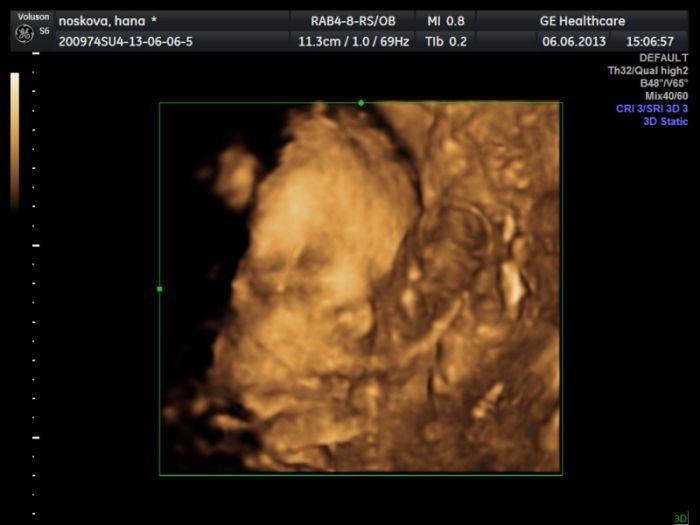

Co nového maminy? Byli jsme ve čtvrtek na tom 3D utz a popravdě, měla jsem o tom trošku jinou představu, ale svůj účel to svým způsobem splnilo, jen nám bohužel nikdo nepotrvdil to pohlaví, takže jsme stále v neúplné jistotě

Nějak s námi opět moc nespolupracoval a vystrkoval na nás prdýlku stydlín jeden!

Musíme vydržet hold ještě nějakou chvíli no... Dám Vám sem jednu fotečku, jak na nás krásně špulí pusinku pusinka naše!